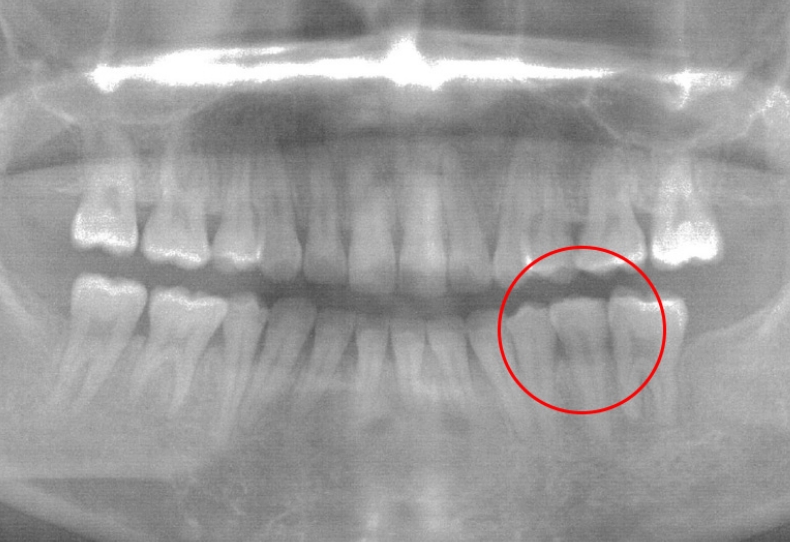

Case4 / 下右第1大臼歯欠損・下右親知らず埋伏

治療前

| 主訴 | 下右第1大臼歯欠損 下右親知らず埋伏 |

|---|---|

| 治療内容 | 倒れている下右親知らずを起こし、3D-LST矯正治療法を用い奥歯を大胆に移動。 |

| 患者年代・治療期間 | 30代女性・2年4ヶ月(難治症例) |